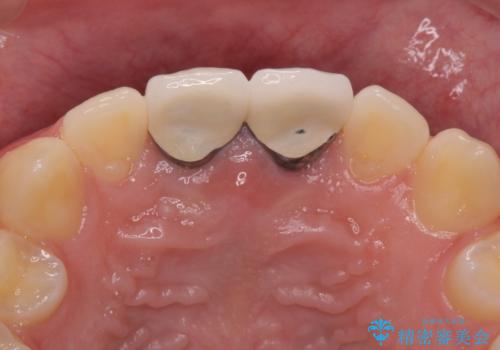

二本とも神経の治療のやり直し(再治療)を行ってからセラミックを入れています。

今回は、前歯のかみ合わせが深く、下の前歯が根元にかみこむような状態だったため、オールセラミックは難しく、メタルボンドクラウン(金属の裏打ちにセラミックが盛ってあるクラウン)となりました。